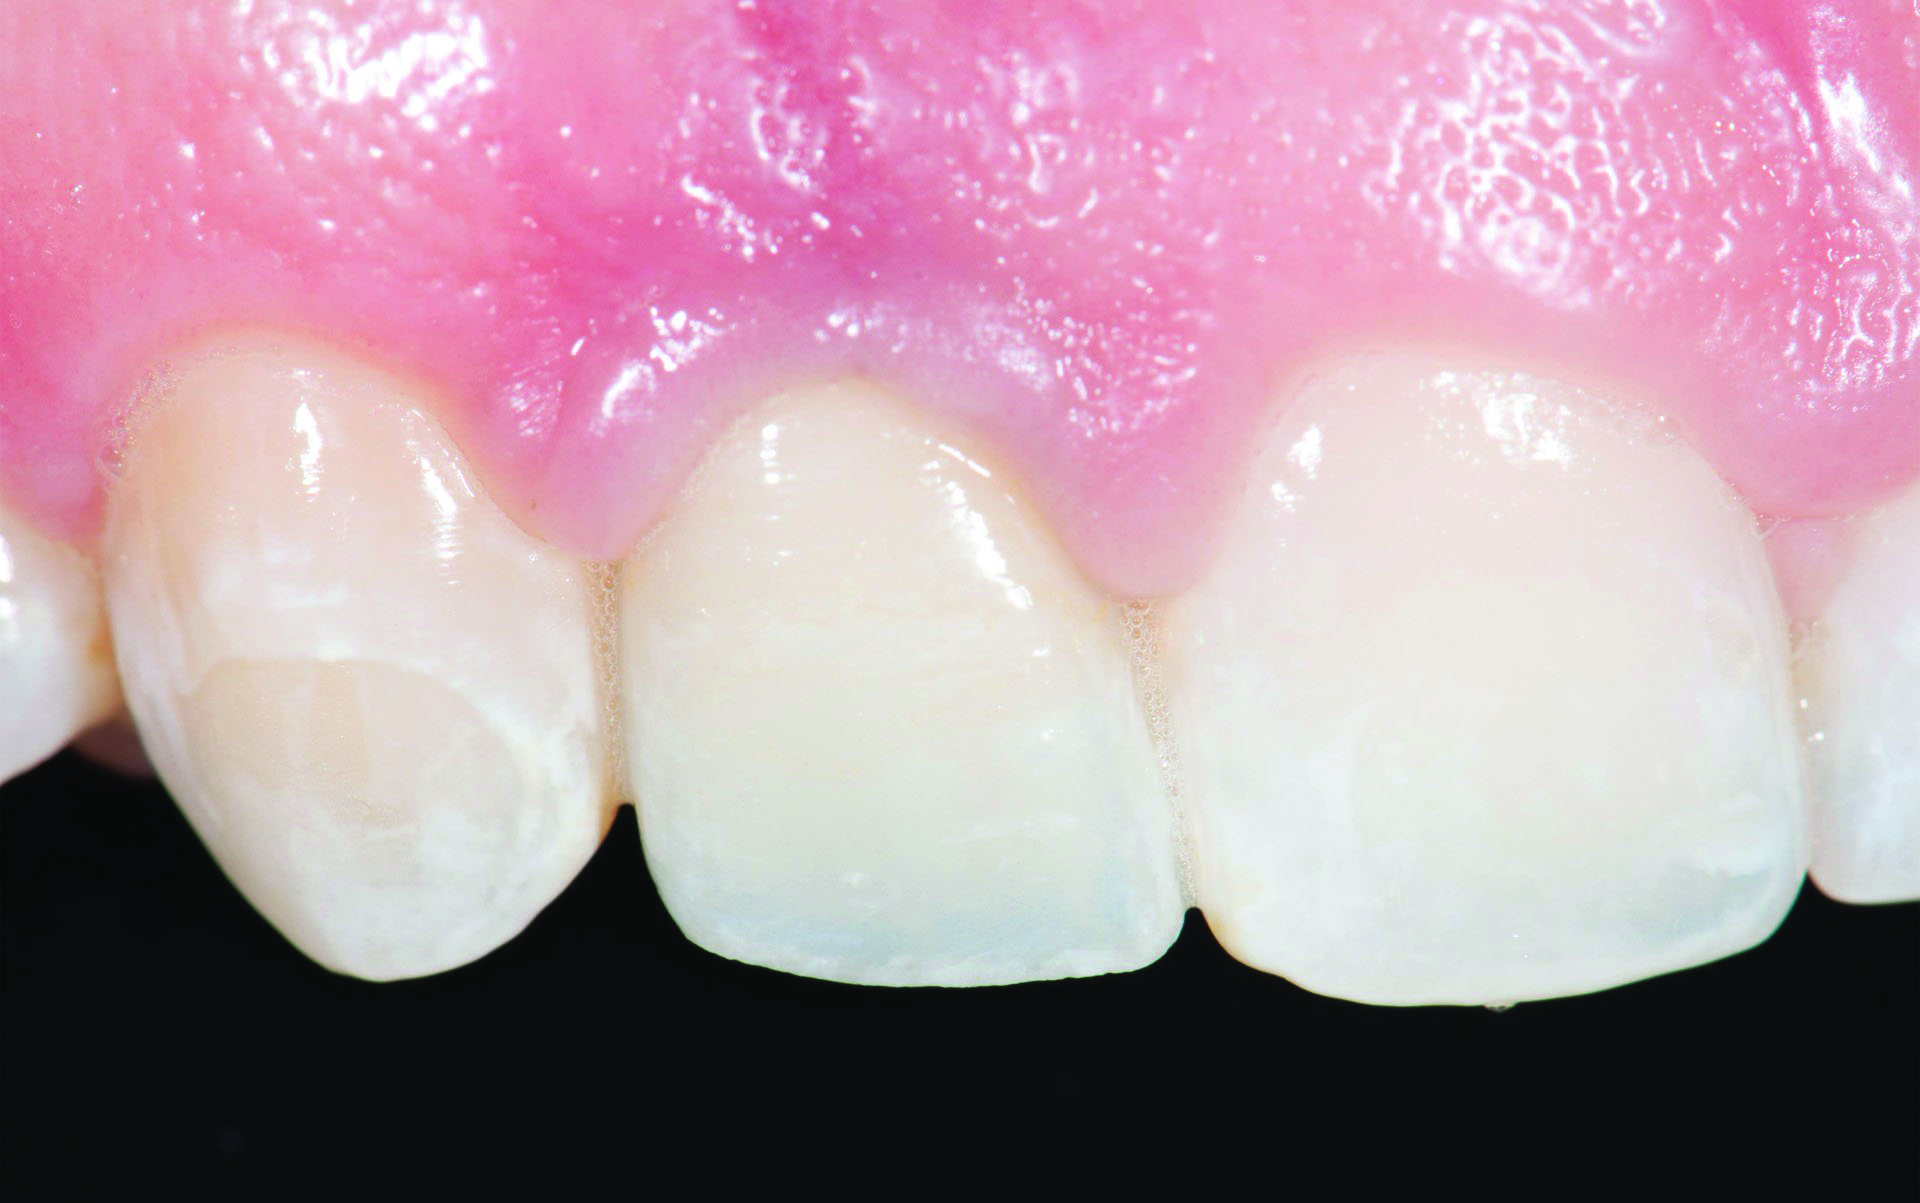

Fig 2. Titanium abutment is visible through the soft tissue of an anterior implant restoration on the maxillary left lateral incisor.

Figure 2

Titanium show-through of the gingival can also be an issue. Figure 2 demonstrates a titanium abutment that is visible through the soft tissue of an anterior implant restoration. Results of the aforementioned survey disclosed that 42% of clinicians place the abutment margins 1 mm subgingival and the remainder are placed 0.5 mm subgingival (33%) or equigingival (25%).1 Placing the margins deeper within the sulcus may help to hide the titanium; however, margins placed 1 mm and 3 mm subgingivally had about 12 times or 24 times more undetected excess cement, respectively, than equigingival margins.5